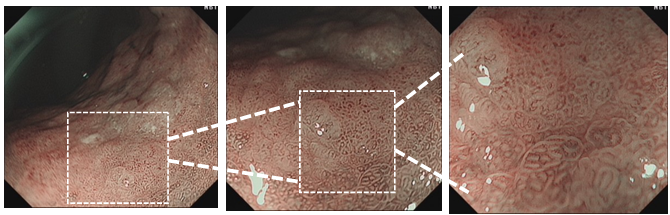

辅助检查:凝血功能、肝肾功、电解质等检查未见异常,血常规未见明显异常。入院后完善胃镜检查:萎缩的胃黏膜背景下,胃体小弯中上段偏后壁可见类圆形的黏膜色泽混杂的平坦型病变,表面伴有轻微隆起的结节样颗粒,大小约2.0×1.8 cm,反复吸气和充气后病变延展性好。靛胭脂染色后病灶边界不清晰,NBI下病灶可见边界清晰的茶褐色区域。予以局部取材送检,病理结果回示:黏膜内癌-中高分化。同时尿素酶试验提示患者Hp阳性。

该患者为Hp感染后萎缩性胃炎背景下胃体小弯侧0-Ⅱb型病变,白光下可见胃体小弯侧平坦型病变,色泽以红为主,边界较清晰,表面伴有轻微隆起的颗粒样结节,反复吸气充气后病变延展性好,黏膜轻微增厚,并且无明显凹陷及隆起,无皱襞集中表现,故深度考虑为黏膜内癌;M-NBI下MS可见不规则卵圆形腺管结构,呈绒毛状,无融合,MV可见不规则扭曲,粗细不均的血管局限于卵圆形腺管内(VEC),故分化类型考虑,分化型为主(乳头状腺癌),伴有少量低分化腺癌可能。结果从病理活检中得以证实。